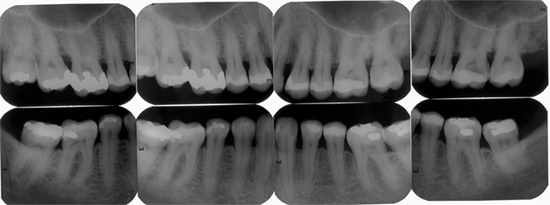

Ortho X - Radiografia Periapical

Tem como objetivo visualizar as ápices das raízes dos dentes e das estruturas que o rodeiam. É utilizada para pesquisa e lesões periapicais e periodontais, fraturas, anomalias, reabsorções e outras lesões que atingem o orgão dental.